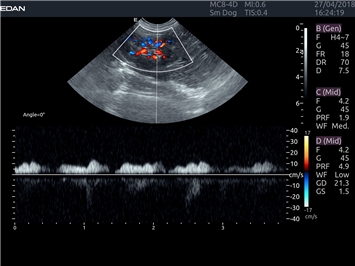

Трехмерная реконструкция ЦДК:

Да

Энергетический допплер:

Высокочастотный импульсный допплер:

Нет

Цветовой допплер:

Постоянно-волновой допплер:

Импульсно-волновой допплер: